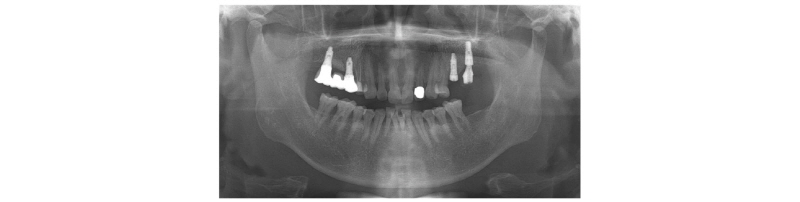

국소 마취 후 판막을 거상하고 임플란트를 확인하였다(Fig. 2A~2C). 트레핀 버를 이용하여 임플란트를 제거하였고 이때 #17 부위에서는 상악동이 천공되었다(Fig. 2D). 골창 내부로 콜라겐 스펀지를 삽입하였다(Fig. 2E). 상부에 이종골 이식재(deproteinized bovine bone mineral, DBBM)을 적용하고 titanium mesh로 고정하였다(Fig. 2F). 이후에 흡수성 콜라겐 차페막을 적용하고(Fig. 2G), 흡수성 봉합사 4/0 vicrly로 봉합하였다(Fig. 2H). 1주일 뒤 내원했을 때 수술 부위 이상소견 관찰되지 않았다(Fig. 2I). 수직적으로 6 mm, 협설 방향으로 8 mm, 근원심 방향으로 23 mm 정도의 골증대를 이루었다(Fig. 3).

4달 뒤, 내원하였을 때 수술 부위에 특별한 이상 소견 관찰되지 않았다(Fig. 4A). 국소마취하에 판막을 거상하고(Fig. 4B), titanium mesh를 제거하였다(Fig. 4C). #15, #17 부위에 임플란트를 식립하였고(Fig. 4D), apically positioned flap으로 봉합하였다(Fig. 4E). 2달 뒤 체크하러 왔을 때 큰 이상소견 보이지 않았고(Fig. 4F), 임플란트 식립 4개월 후에 최종 보철 시행하였다(Fig. 5).